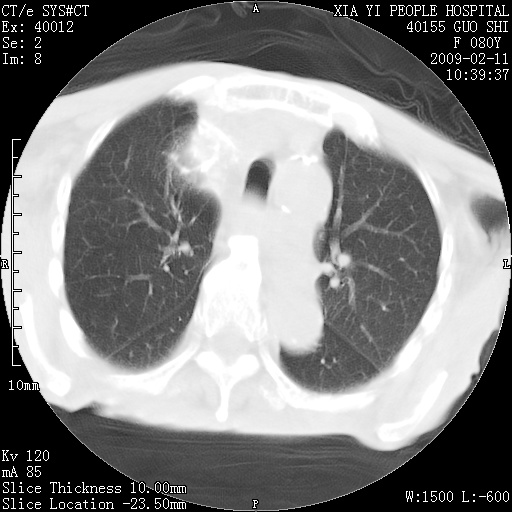

以下是引用随光逐影在2009-2-16 16:34:00的发言:[br]1)考虑右前纵隔皮样囊肿。2)双侧少量胸腔积液。

以下是引用zjzjr在2009-2-16 17:30:00的发言:[br]支持囊性畸胎瘤 双侧少量胸腔积液。